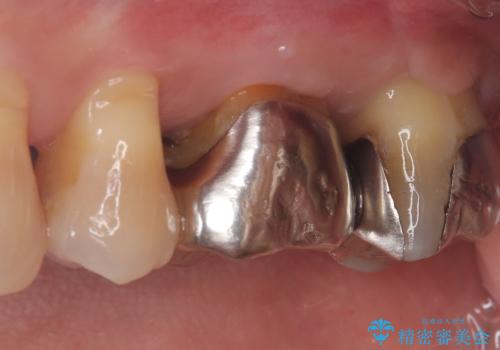

【根管治療】ズーンと痛い歯の治療。

- 奥歯付近がジーンと痛いことを主訴に来院されました。

左上7番の歯は、歯髄検査にて反応を示し、歯周ポケットはありませんでした。

親知らず抜歯を行い、痛みの変化や歯根吸収の有無を確認したのち、抜髄処置を行っています。

症状改善し、遠心の骨の回復も認めます。

バイオセラミックシーラーを使用して根管充填を行っています。